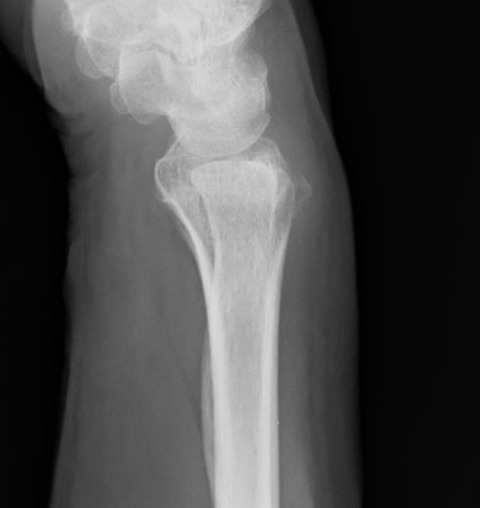

しかし、単純X線像をみると、何となく普通ではありません。??? と思って、側面像を見ると、橈骨遠位端背側の皮質骨が変な感じです。

これって、骨折ではないのか? ご本人に何度も念押ししましたが、やはり転倒等のエピソードはないとのことです。受け答えはしっかりしており、認知症でもなそうです。

念のためにMRIを撮像すると、やはり橈骨遠位端骨折のようです。圧痛点も関節ではなく、橈骨遠位端なので、画像と身体所見が一致しました。